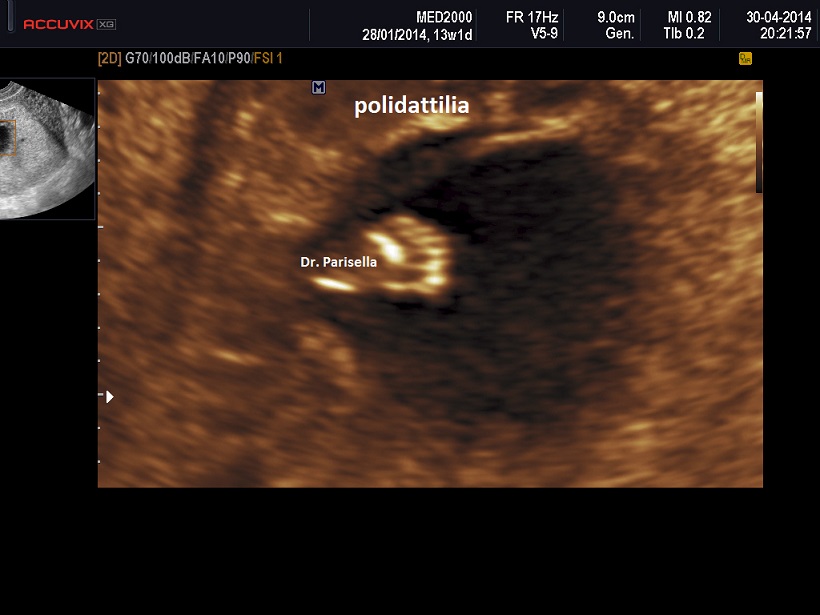

• Displasia scheletrica: ossa lunghe curve, agenesia della fibula, aspetto a ventaglio delle dita dei piedi, polidattilia;